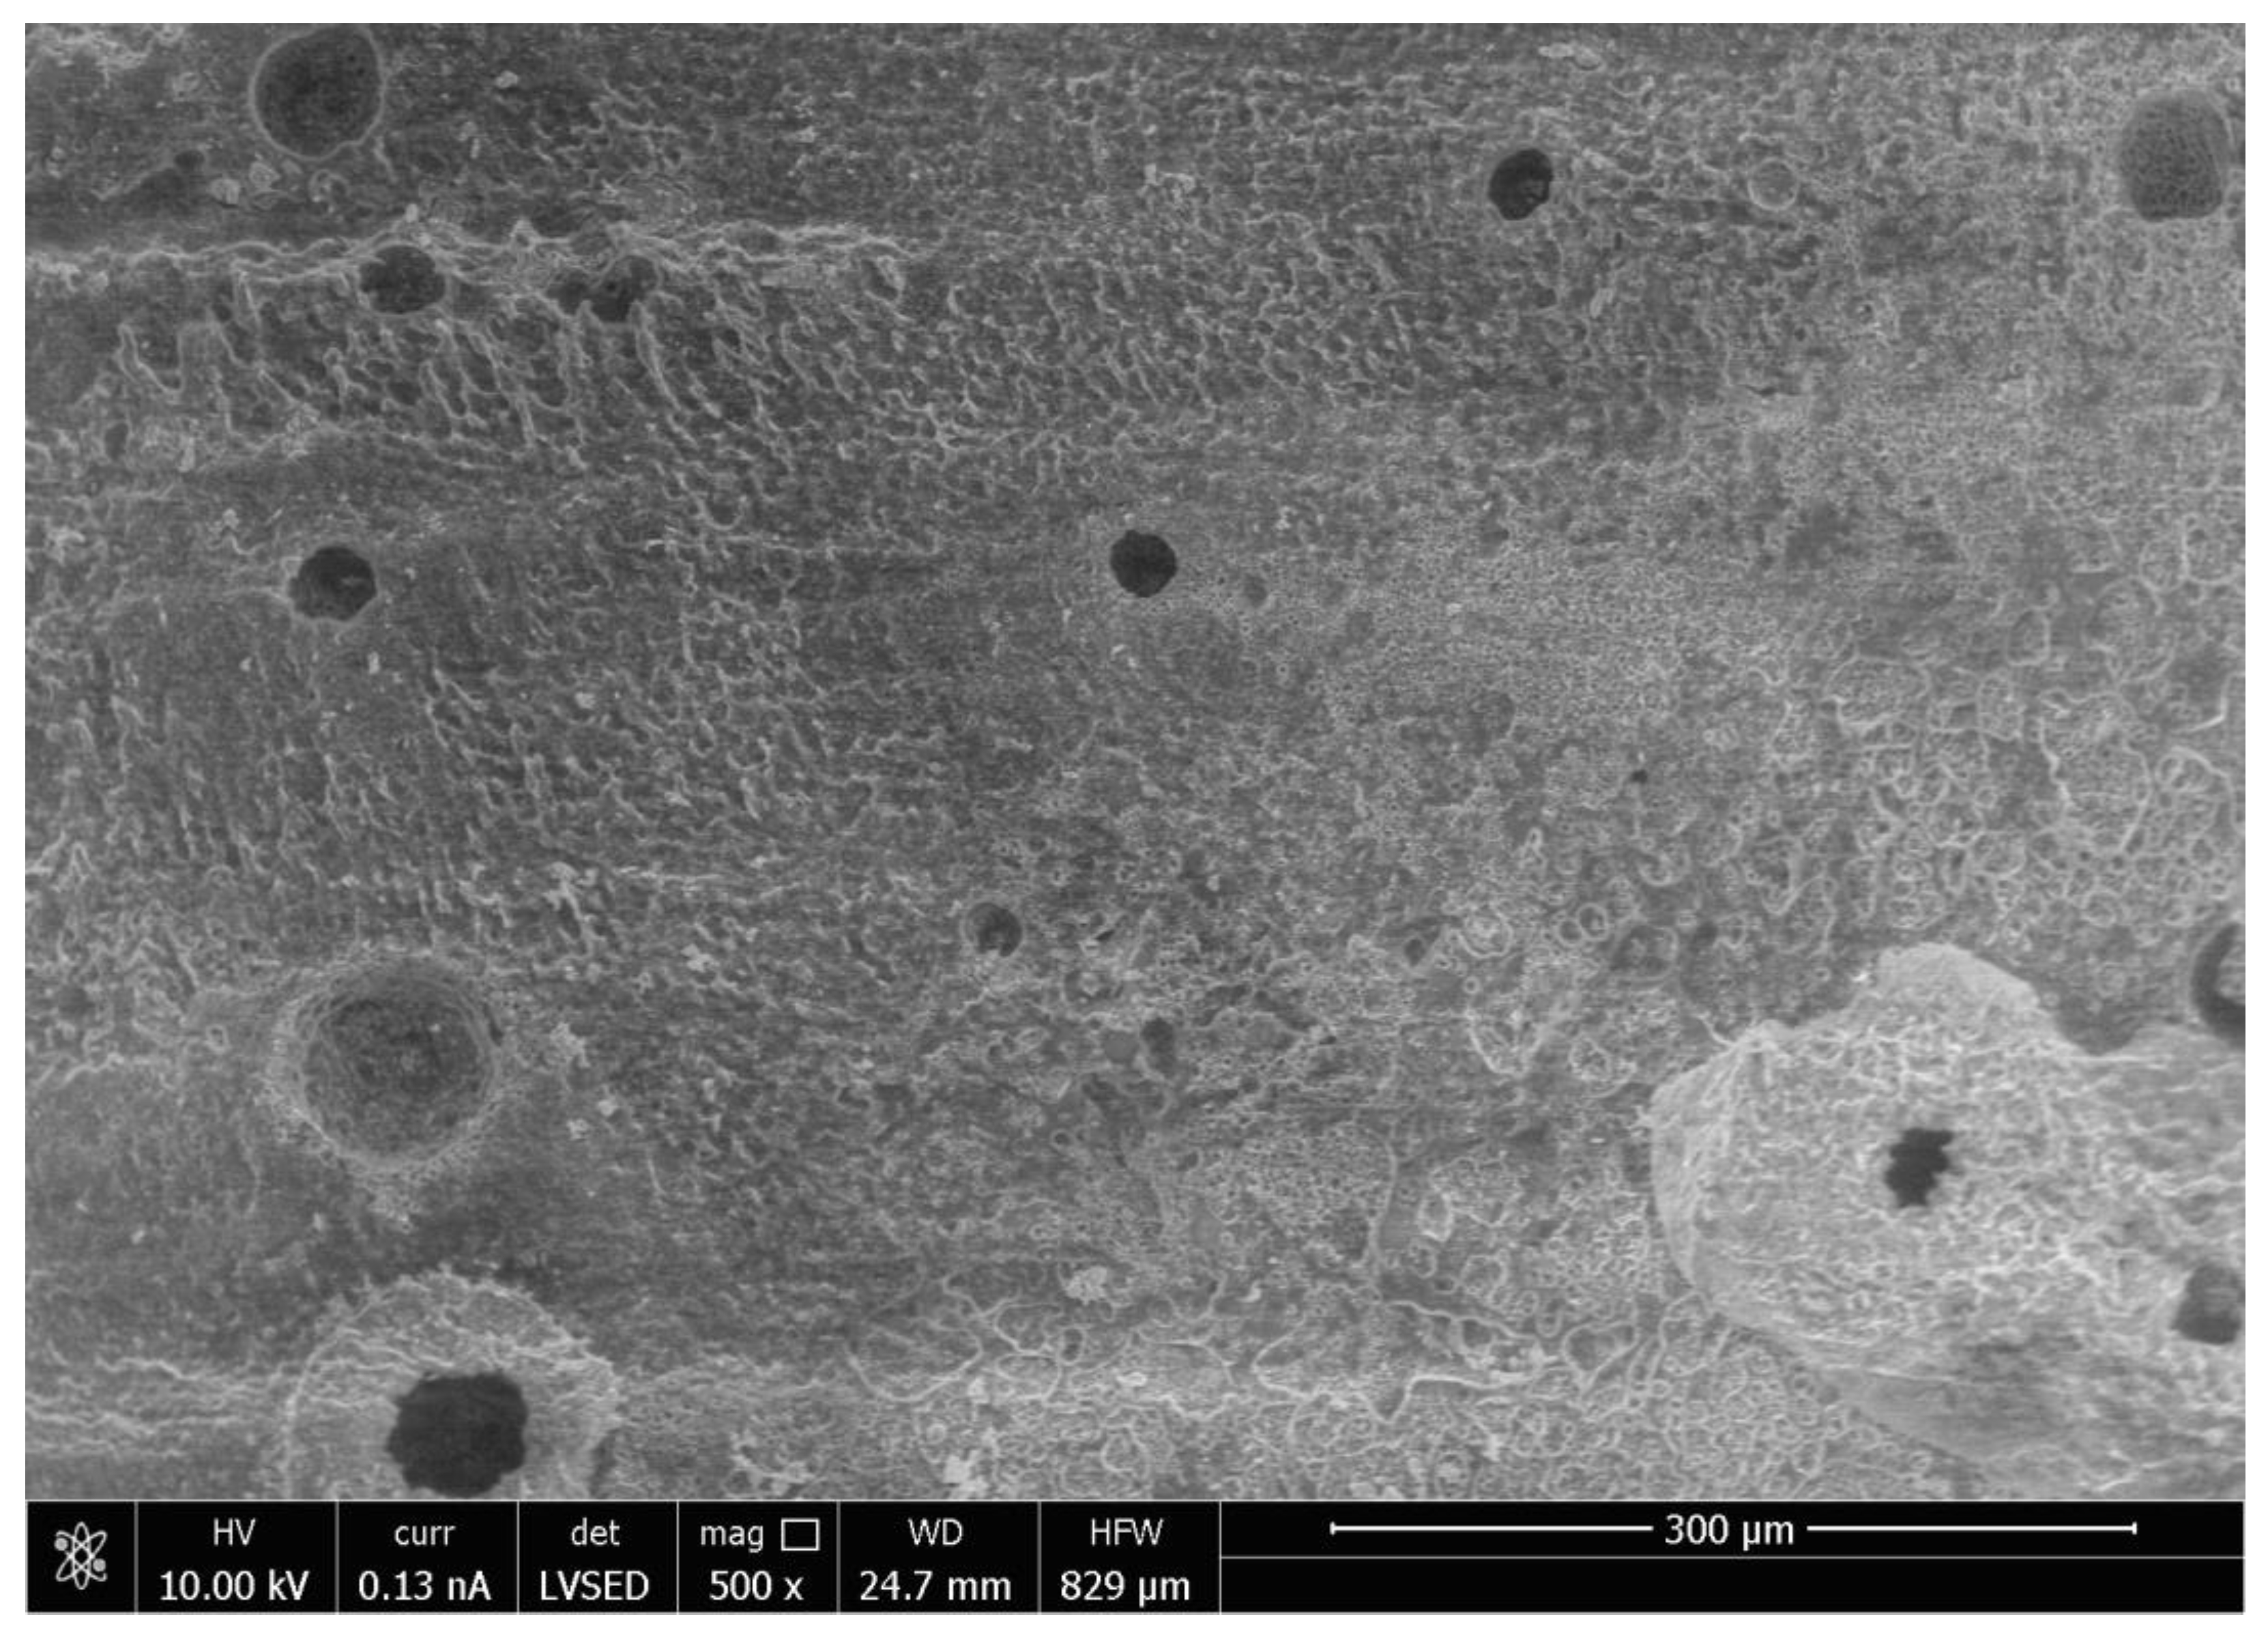

SEM analysis of the abutment teeth demonstrated rotary cutting streaks on the tooth surface at a low magnification of 500× (Figure 5). At higher magnifications (≥5000×), there were more openings of the dentinal tubules observed in the rotary handpiece removal group compared to the laser group. The dentin surface of the specimen from laser crown removal appeared to have a more intact smear layer and residual cement (Figure 6A,B). Crown specimens from the rotary group presented with more crack and crest lines at higher magnification levels (10,000×), indicating possibly more surface damage of the ceramic material compared to the laser group (Figure 7A,B).

Thermal stimulation of pulp tissue can occur during crown removal using both the laser and air rotary handpiece techniques. An increase in pulpal temperature by over 5.6 °C is thought to induce pulpal damage [25,26,27] and a pulpal temperature of over 42 °C can cause increased blood flood into the pulp or pulpal hyperemia, resulting in irreversible pulp damage [28]. Increases in pulpal temperature during removal with either the laser or rotary handpiece technique did not exceed 27.7 °C and the temperature change for both methods is less than 2–3 °C. Laser irradiation also showed more variation in temperature and higher temperature readings compared to air rotary removal. Differences in increases in pulpal temperature can be attributed to the functionality of each device. Higher temperature readings associated with laser irradiation can be attributed to longer procedure times, less water spray for cooling, and higher energy needed for crown removal. When crowns are removed with an air rotary handpiece, the energy is absorbed on the surface of the crown and further away from the pulp. Laser energy is absorbed by the underlying chromophore (cement), which is closer in proximity to the pulpal tissue, and thus contributes to greater increases in pulpal temperature during laser crown removal. Primary anterior teeth have a thin layer of remaining dentin that overlies the pulp chamber following tooth preparation, thus the higher temperature change in this group during laser irradiation can probably be attributed to the thin dentinal layer between pulp and luting cement. Adequate water spray is essential to prevent thermal damage to pulpal tissues. Thinner dentin and larger pulpal chambers, especially in pediatric permanent teeth, may be prone to thermal irritation during laser irradiation [29]. The small anatomical primary tooth crown can also be a factor. Thus, it may be preferable to decrease laser setting parameters in the pediatric population, which may lengthen the time required for crown debonding. Pulpal irritation can also be caused by the direct irritation of the dentinal tubules. The SEM analysis of an abutment tooth in the rotary handpiece group revealed greater opening of the dentinal tubules compared to the laser group. The laser removal method appeared to leave a smear layer and cement layer covering the dentin surface that was not apparent in the rotary handpiece group. Greater amounts of open dentinal tubules and lack of a smear layer can result in a higher possibility of post-operative sensitivity following crown removal.

Similar to previous studies, crown removal by laser does not appear to damage the retrieved crowns or the underlying tooth structure [3,6,18,30]. In our study, SEM analysis demonstrated that laser irradiation of zirconia crowns showed no underlying tooth damage and fewer surface irregularities of the crown surface compared to air rotary removal. Evidence of changes in tooth structure at low magnification following removal with a rotary handpiece proves there is a risk of damaging the tooth during crown removal. However, if a crown was to be retrieved due to recurrent caries, then the extent of the caries will impact the dentin surface and smear layer, irrespective of what crown removal technique is employed.

Figure 5. Scanning Electron Microscope Image of the Surface of the Tooth at Magnification 500× Following Crown Removal with Air Rotary Handpiece.